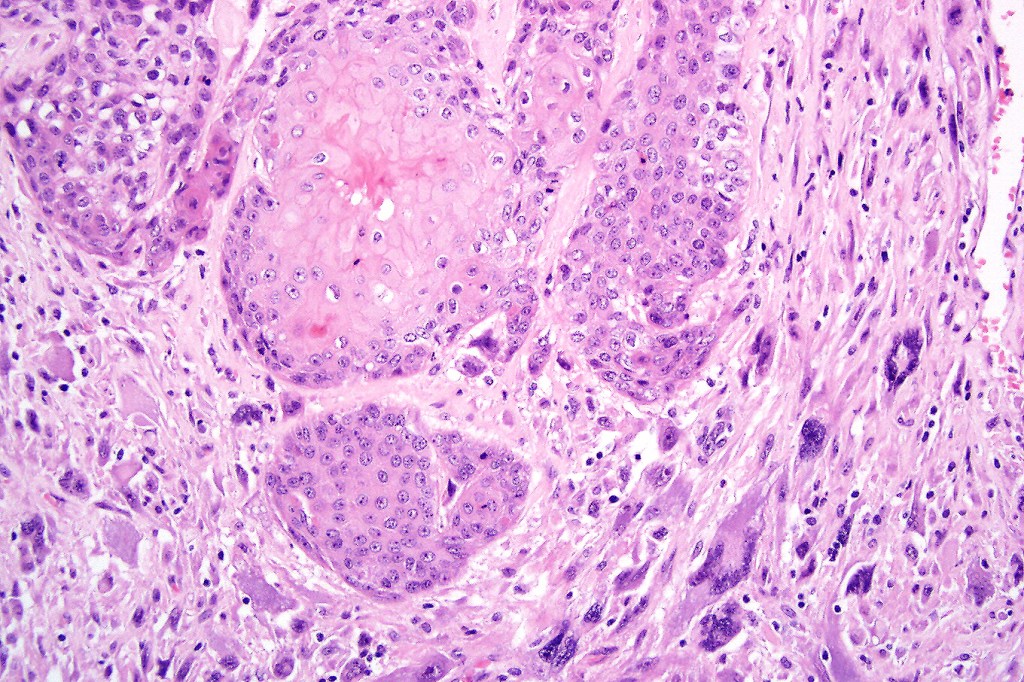

Carcinosarcoma

Cutaneous carcinosarcoma (metaplastic carcinoma, carcinoma with heterologous differentiation)

Histological features

•Osteoid

•Chondroid

•Smooth muscle

•MFH-like features with osteoclasts

•Neural differentiation